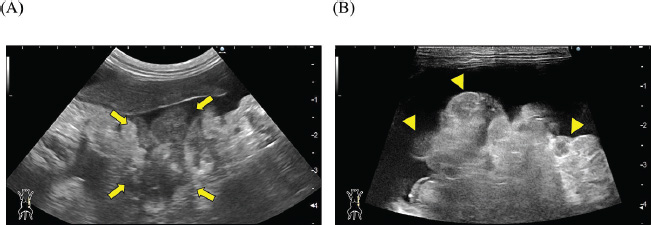

A 2-year-old castrated male domestic shorthair cat, weighing 5.3 kg, presented with a 2-month history of abdominal distension and a 4-day history of anorexia. There was no history of illness or abdominal surgery. Physical examination revealed severe abdominal distension with a fluid wave and mild hypothermia (37.1°C). Blood tests revealed mild elevations in blood glucose (178 mg/dl; reference interval 71–148 mg/dl) and serum amyloid A (5.27 µg/ml; reference interval <3.75 µg/ml) levels, while lipase activity was within normal limits (23.9 U/l; reference interval <30 U/l). Abdominal radiography revealed increased radiopacity and digestive tract consolidation (Fig. 1). Abdominal ultrasonography revealed severe ascites, small intestine hypoperistalsis, pancreatic enlargement, and irregular thickening of the peritoneum with several nodules (Fig. 2). Echocardiography revealed no abnormality. In the ascitic fluid analysis, the total nucleated cell count was 1,000 cells/μl with no evidence of neoplastic cells or bacterial infection, and the specific gravity of the supernatant was 1.024, confirming the ascites as a modified transudate (Fig. 3). Feline infectious peritonitis was considered unlikely due to the absence of feline coronavirus genes in the ascitic fluid and no elevation in blood anti-coronavirus antibody titers. Based on the imaging findings, such as peritoneal thickening, gastrointestinal tract consolidation, and severe ascites, EPS was initially suspected. These findings are consistent with the typical presentation of EPS, characterized by fibrotic thickening of the peritoneum and encasement of abdominal organs (Gremillet et al., 2022). However, the possibility of malignancy was deemed unlikely due to the cat’s relatively young age. A trial treatment with prednisolone (10 mg/head, q24 h) and enrofloxacin (25 mg/head, q24 h) was initiated to manage the suspected inflammatory process and potential bacterial infection, respectively. However, no clinical improvement was observed, suggesting that the underlying condition might be more complex than initially suspected. A non-sedated computed tomography (CT) scan was performed to obtain more detailed diagnostic information on day 12 after presentation. A Siwtenn-slice multi-slice CT scanner (Aquilion™ Lightning, Canon Medical Systems, Japan) was used without anesthesia, with the patient restrained in an acrylic cage (CT capsule, Terucom, Japan). The following technical parameters were used: rotation time=0.75 s; slice thickness=1 mm; reconstruction interval=0.5 mm; table speed=16 mm/rotation; helical pitch=16.0; X-ray tube voltage=120 kV; and X-ray tube current=100 mA. The CT scan revealed a tumor-like enlargement of the pancreas, irregular scattered nodular formations aggregating dorsally in the peritoneum, and ground-glass opacity in the right lower lobe of the lung (Fig. 4). Because angiography was not performed, the vascular characteristics and more detailed differentiation of the soft tissue masses could not be assessed. A pancreatic tumor was suspected; however, diagnostic and therapeutic surgical interventions were deemed difficult due to the animal’s condition. In addition, the owner declined further invasive procedures, such as fine-needle aspiration or laparoscopy. Despite prednisolone treatment (5 mg/head, 24 h), ascitic fluid drainage, and fluid therapy, the cat died 19 days after the first presentation.

Fig. 2. Abdominal ultrasonography. Severe ascites were observed throughout the abdomen. (A) A hypoechoic irregular area (arrow) was observed in the left upper abdomen, which was considered to be an enlarged pancreas. (B) The peritoneum exhibited irregular thickening, with scattered hypoechoic nodular formations internally (arrowhead).